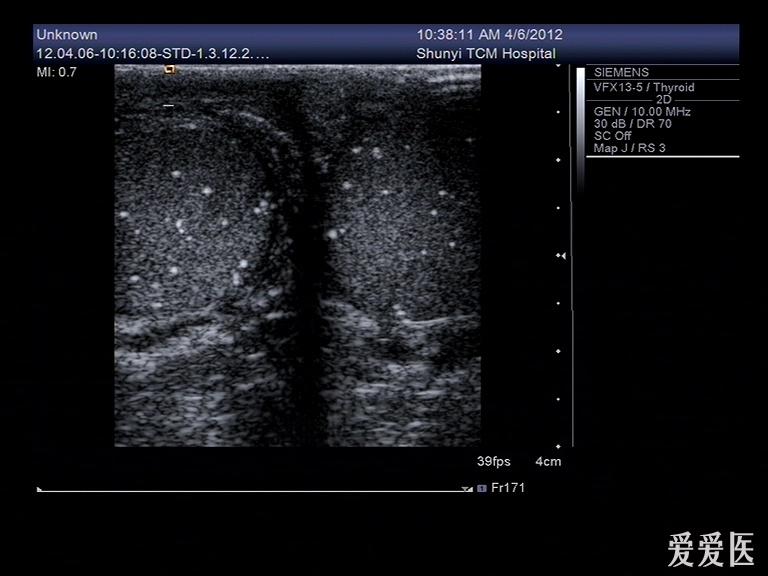

睾丸内点状强回声是什么东西?有图

前几天有个病人来检查,说睾丸疼,大小、形态都没什么变化,就是睾丸内有好多点状强回声,伴彗星尾征。请问这些东西是什么?钙化点?

典型的睾丸微石症

典型的睾丸微石症,有些人和结核有关系!